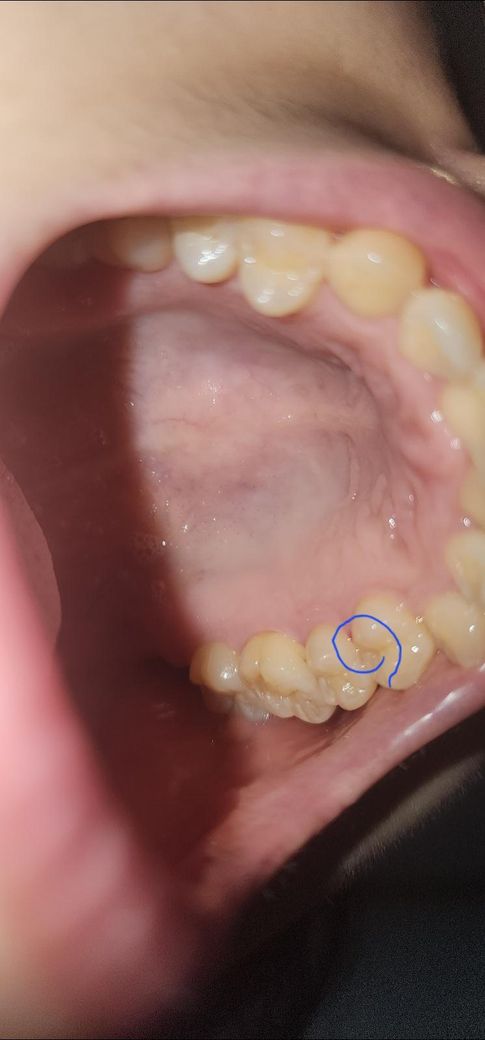

치과에서 잇몸치료후 치위생사가 치아 사이에 치간칫솔 사용해서 2~3회 왕복을 하며 치간칫솔 사용 방법을 알려줬어요 그러고 난뒤 피가 나거나 붓거나 고름이 나오는 증상은 없지만 계속 따가운 느낌이 들어 사진을 찍어보니 어금니 사이 잇몸이 파랗게 동그라미친 부분처럼 빨갛게 상처가 나있네요 이번주 화요일에 치료를 받았구요 계속 좀 불편하고 신경이 쓰이는데 괜찮아질까요? 어떻게 관리를 해야 할까요?

• 1번 째 사진